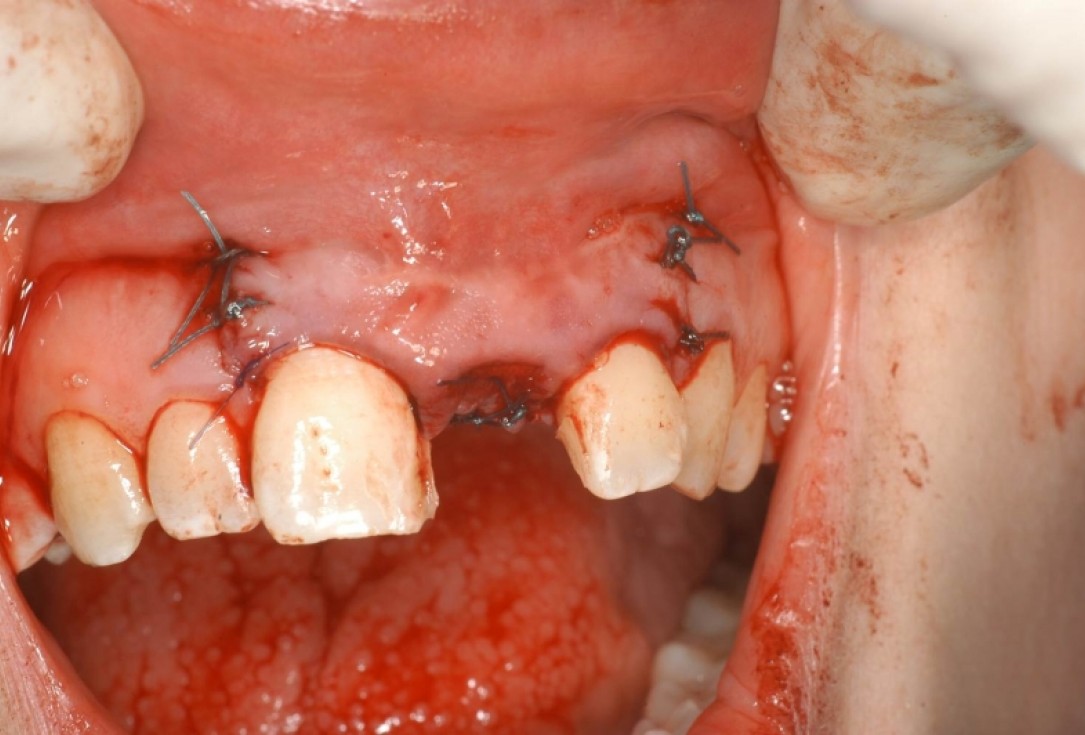

08/12 - Wound closureTreatment of dehiscence defect with cerabone® & Jason® membrane - Dr. M. Steigmann

09/12 - Wound closure, occlusal viewTreatment of dehiscence defect with cerabone® & Jason® membrane - Dr. M. Steigmann